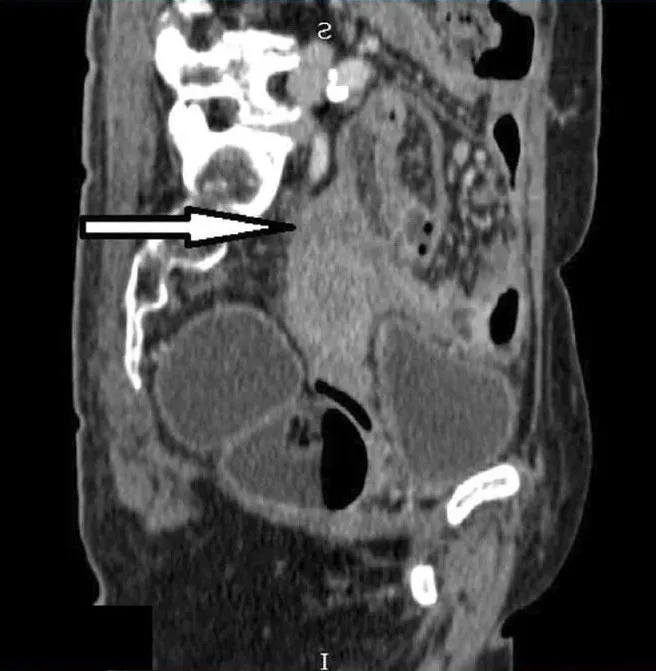

她第一次就诊时的常规胸片(图1)检查偶然发现了右肺肿块。随后的胸部增强计算机断层扫描(CT)(图2)显示肺右下叶后基底段的肺肿块大小为4.7×7.0×7.0 cm(前后×宽度×头尾)。肿块附近也有卫星结节。对肿瘤进行支气管镜活检,组织病理学检查(HPE)结果显示腺癌,证实为原发性肺恶性肿瘤,表皮生长因子受体(EGFR)基因的外显子19缺失。

图4. 矢状面计算机断层扫描显示:子宫底肿块与子宫下方的分界差(箭头)